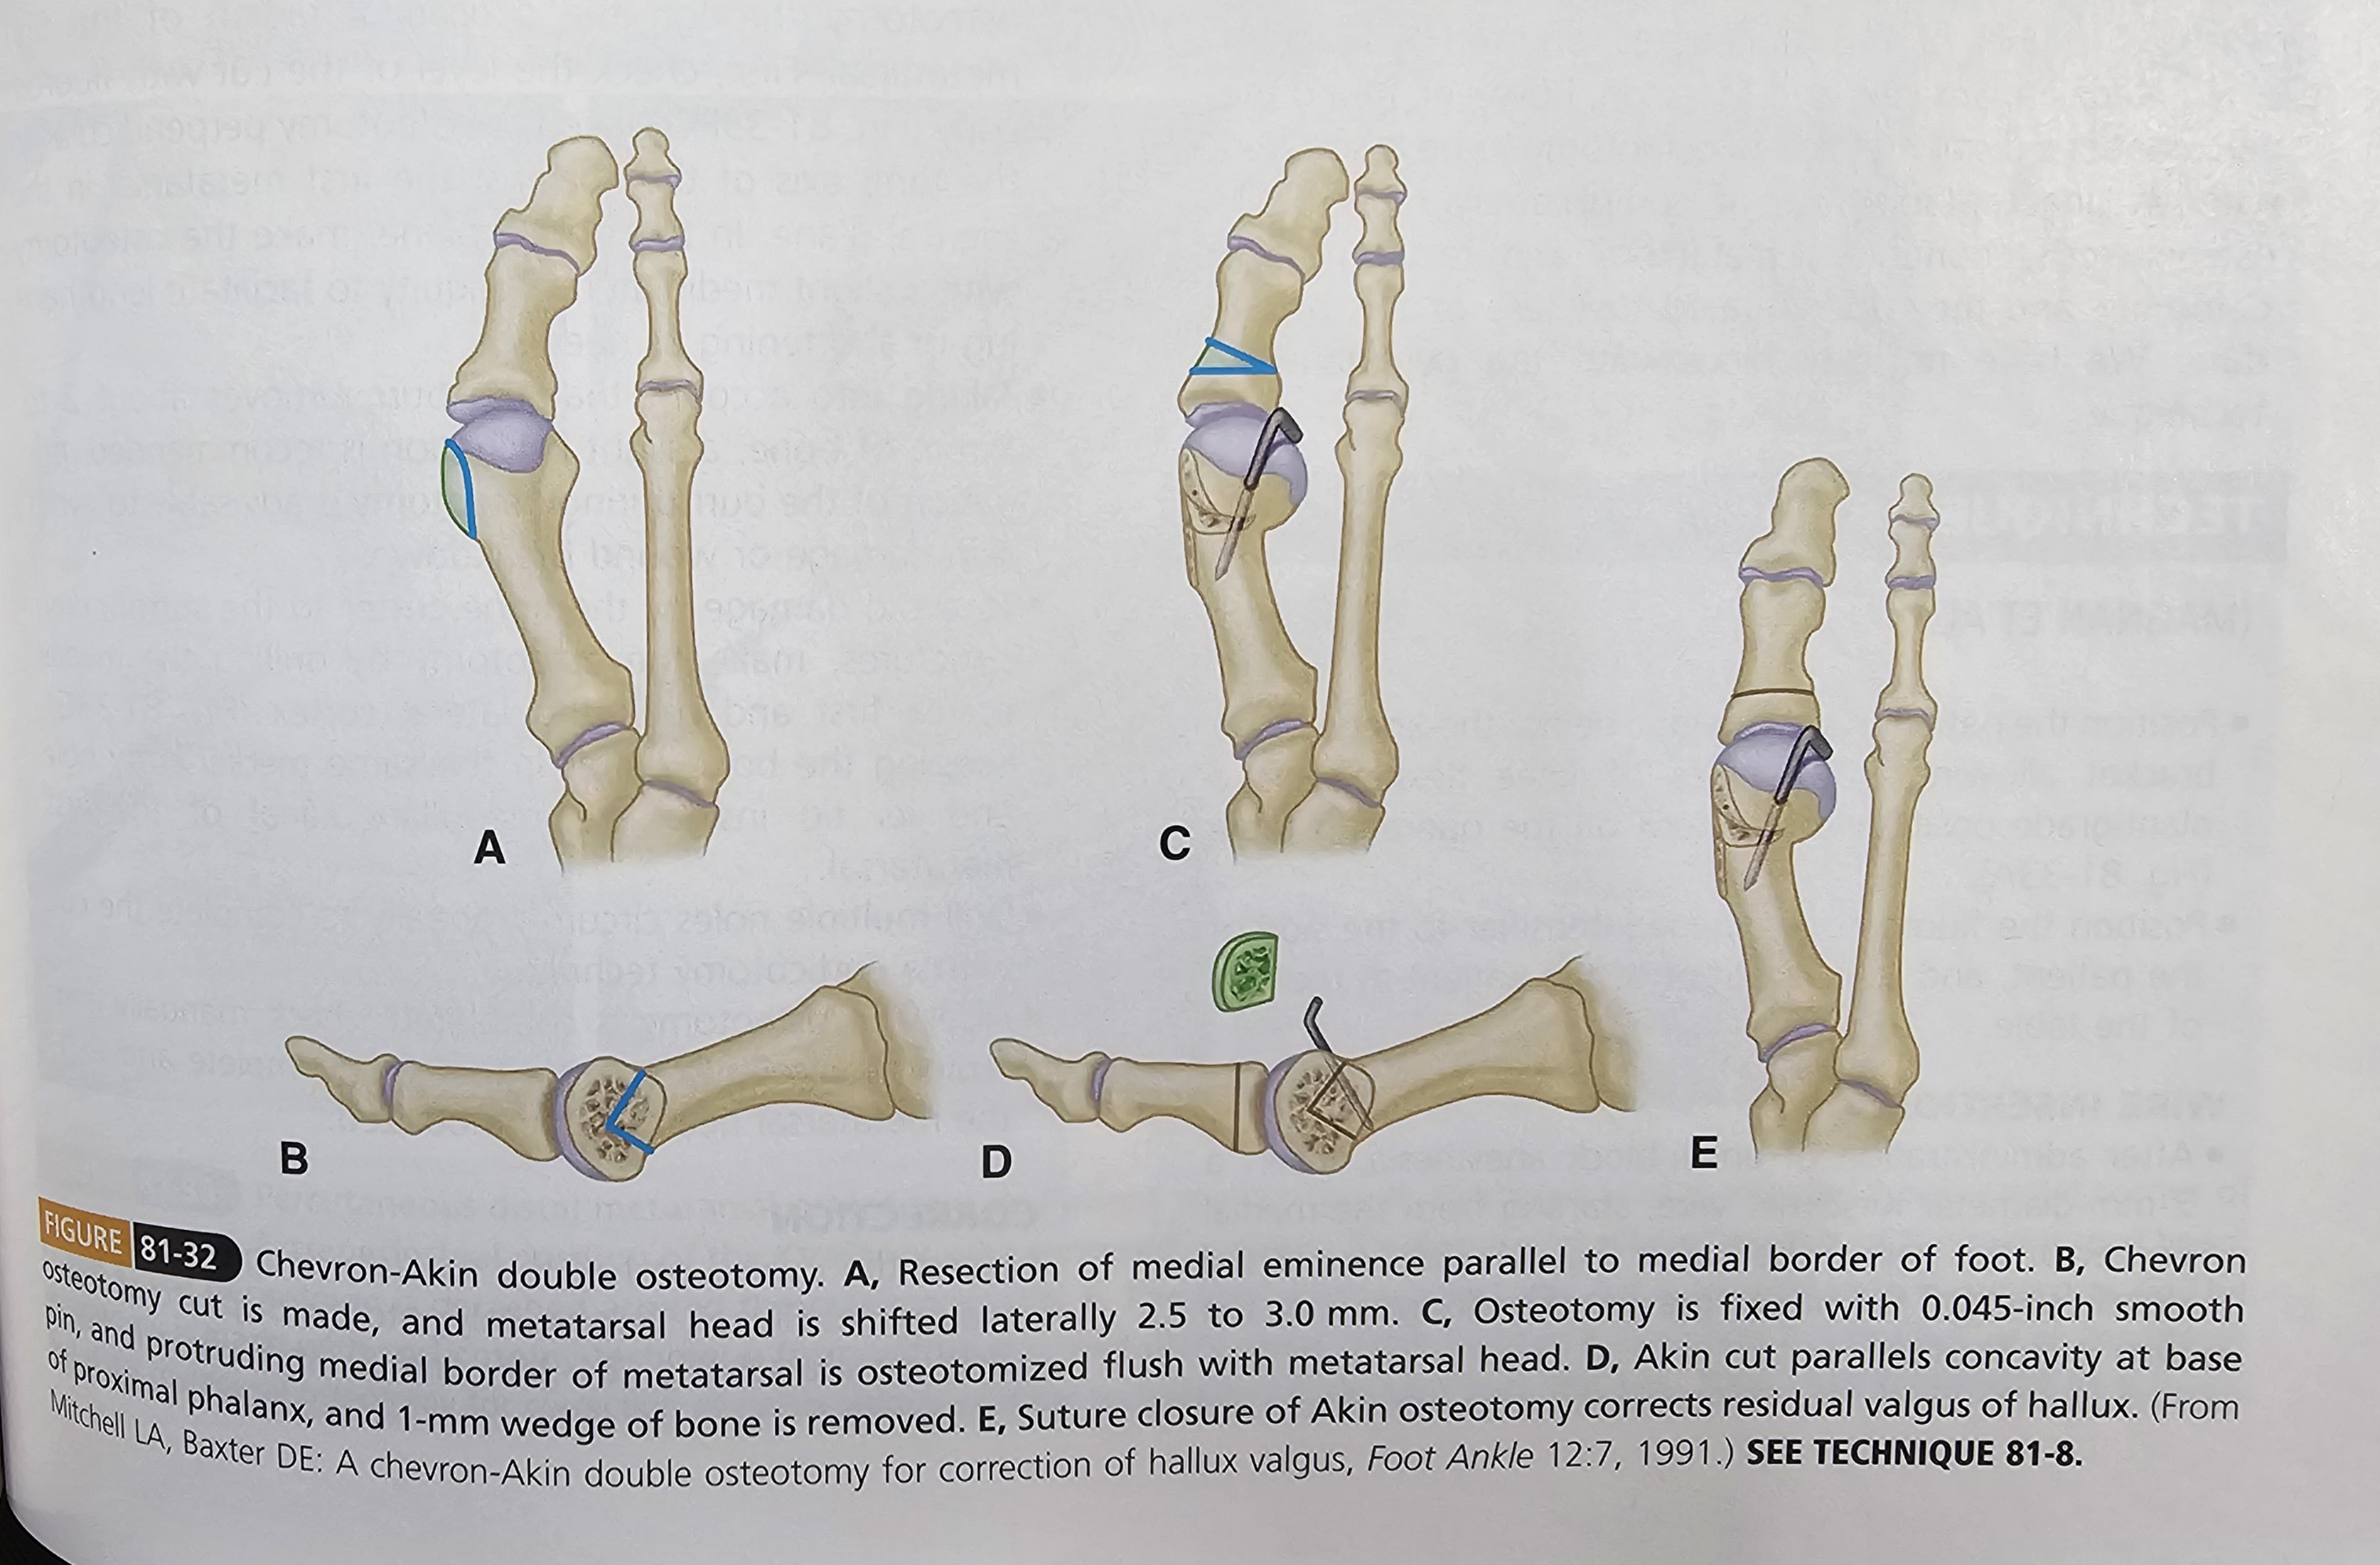

MICA, 3세대 라고 불리는 수술은 Minimally Invasive Chevron & Akin Osteotomy 의 약자 입니다. 말 그대로 작은 흉터로 교정술을 한다라고 보면 될 것 같습니다. 예전에는 갈매기 모양으로 절골술을 하였다면 최근에는 transverse 하게 절골을 하는 것이 유리하다는 논문들이 나오고 있습니다.

3세대와 비교하여 특별하게 크게 달라진 것은 없으나 임상적 예후가 좋은 것으로 논문이 나왔으니 앞으로는 이러한 수술법도 많이 늘어날 수 있을 것 같습니다. 1991년 이런 미세 수술이 발명된 이후, 이런 작은 발전들이 모여 현대 수술기법이 되었을 것 입니다. Akin 은 기존 그대로 open wedge style로 추가적인 HVA을 교정해 줍니다.